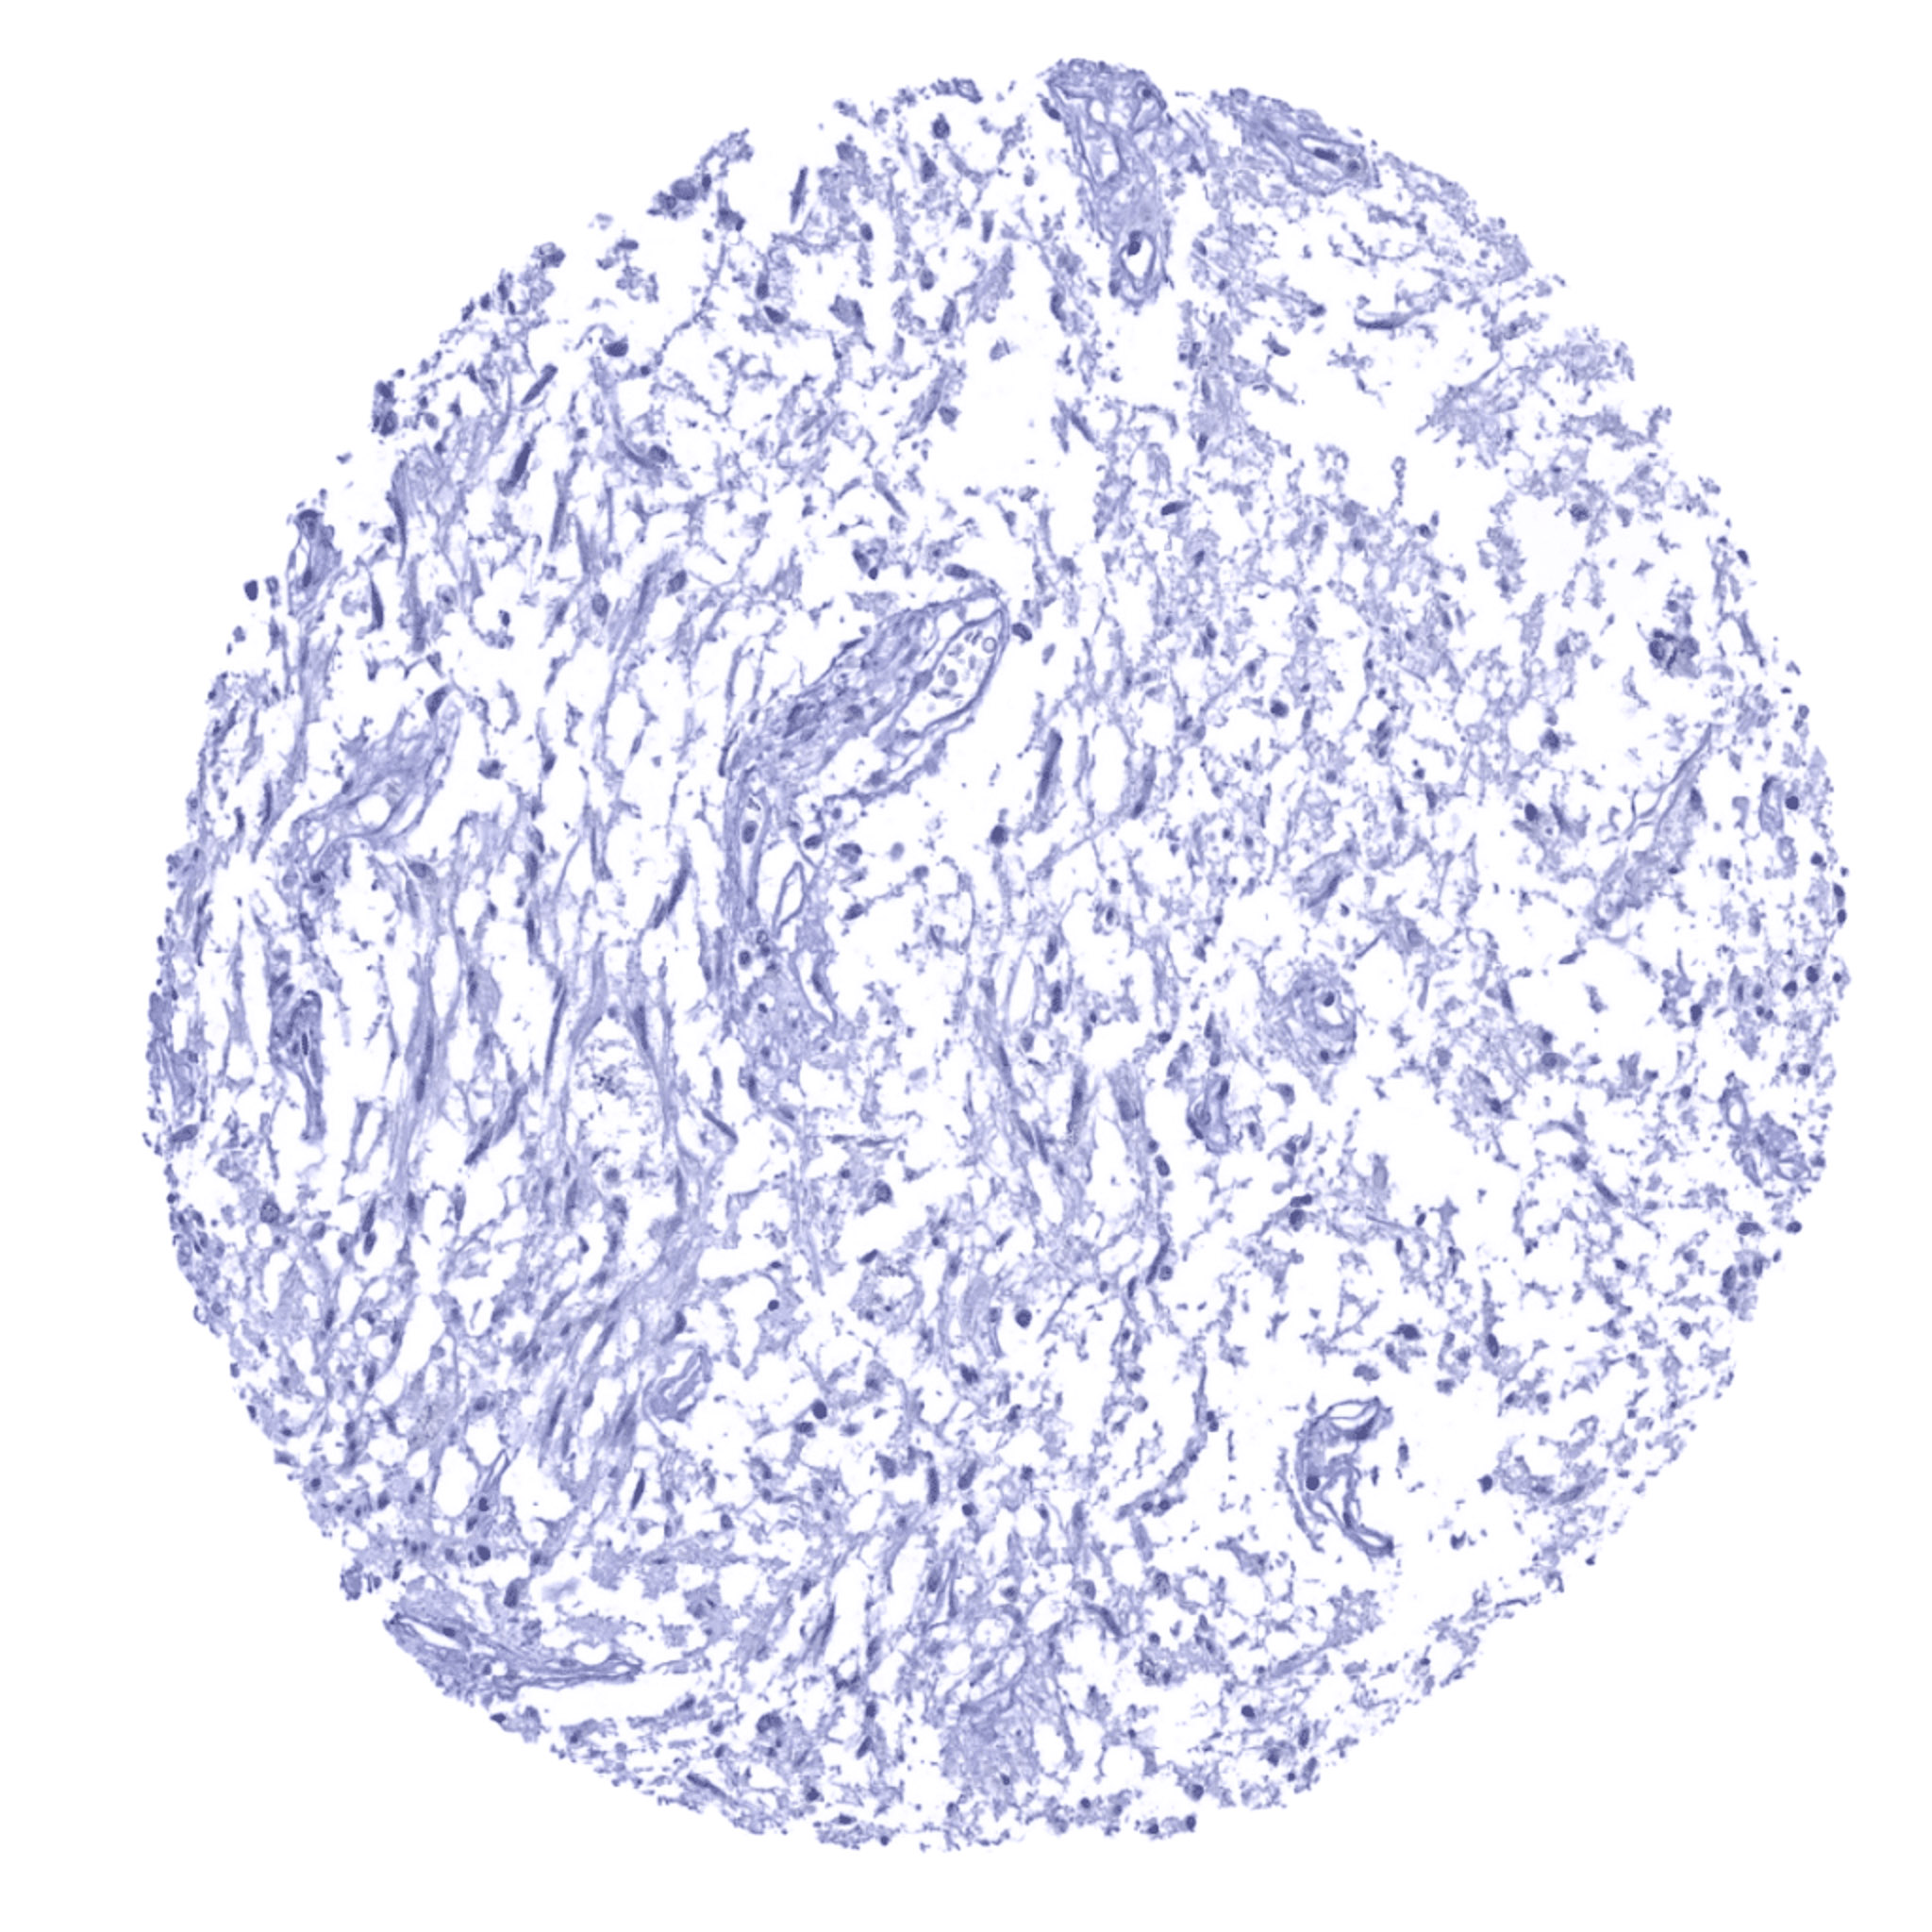

Bone marrow